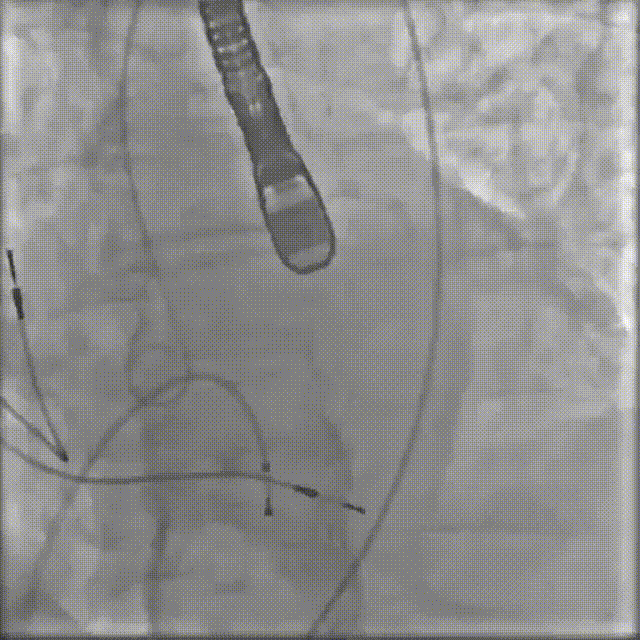

2026年伊始,TaurusTrio经导管主动脉瓣系统在武汉大学人民医院,中国科学技术大学附属第一医院,安徽医科大学第一附属医院,安徽医科大学第一附属医院北区,首都医科大学附属北京安贞医院南充医院,海南省人民医院等多家临床中心成功开展上市后全国首批植入。这不仅是TaurusTrio正式走向广泛临床应用的重要里程碑,更标志着中国单纯主动脉瓣反流介入治疗正式迈入了“心键合璧”的全新纪元。